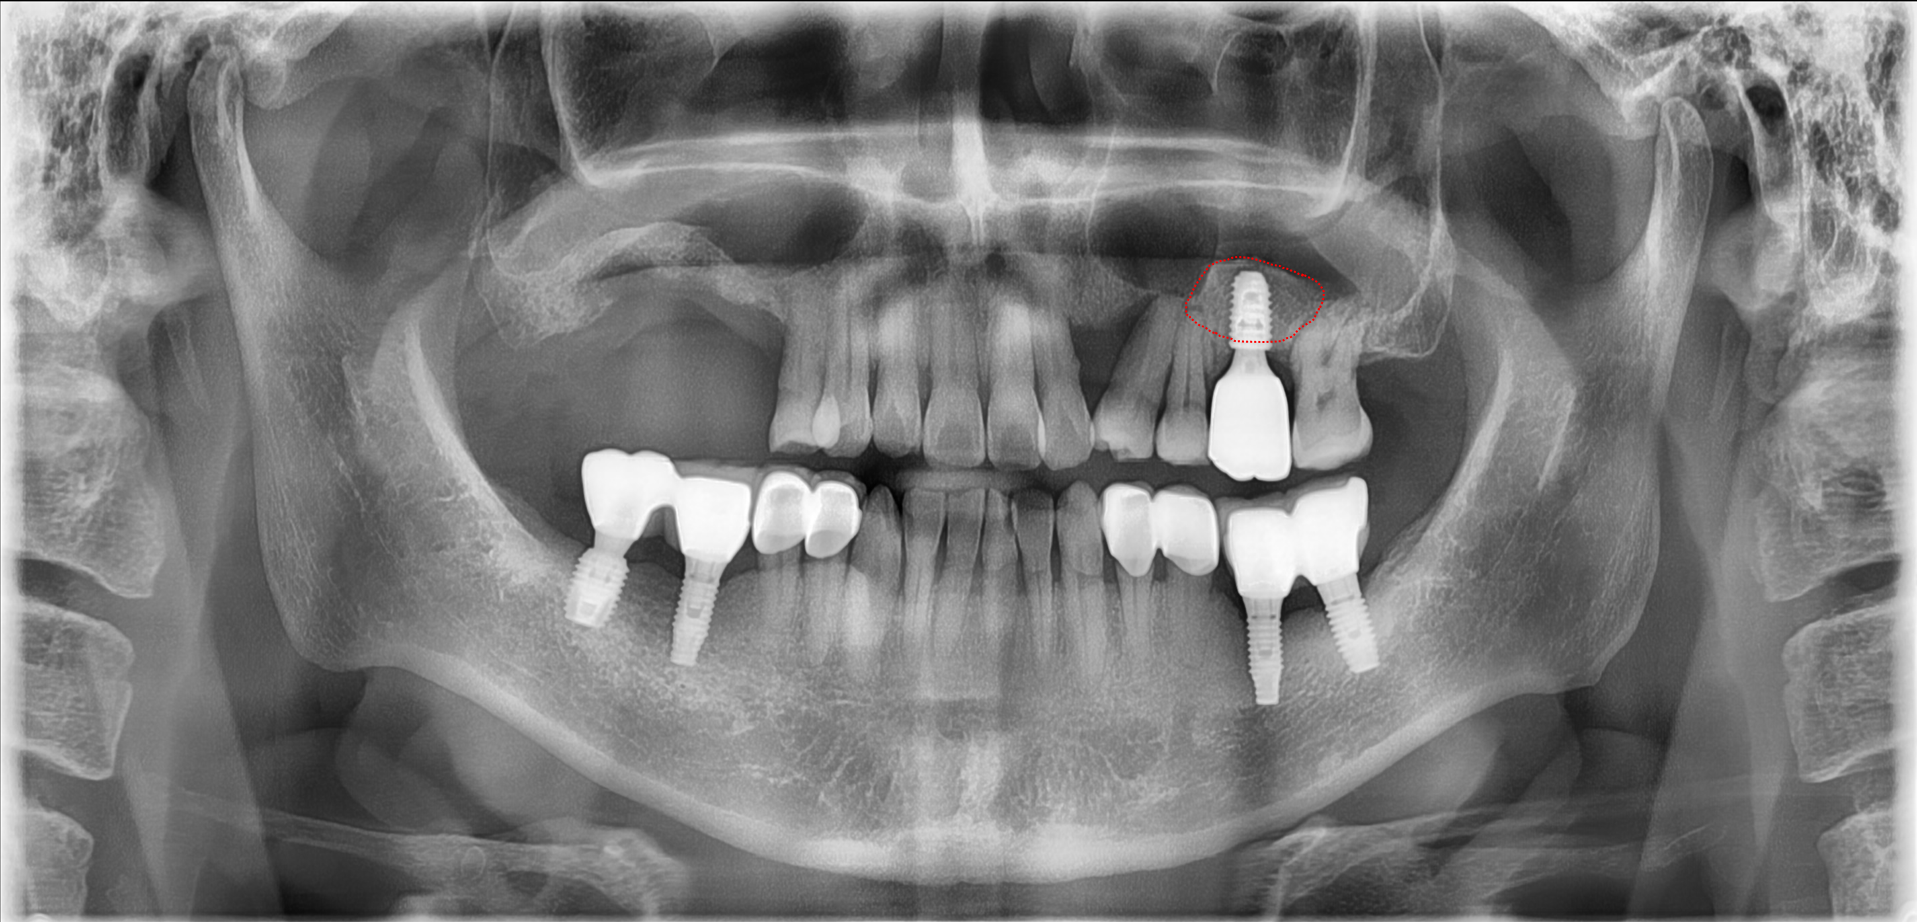

<치료 후>

붉은 점선 부위가 상악동 골이식으로 새롭게 뼈가 생생된 부분입니다.